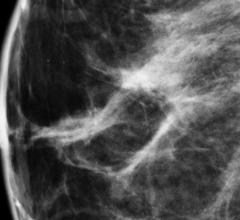

Despite decades of progress in breast imaging, one challenge continues to test even the most skilled radiologists ...